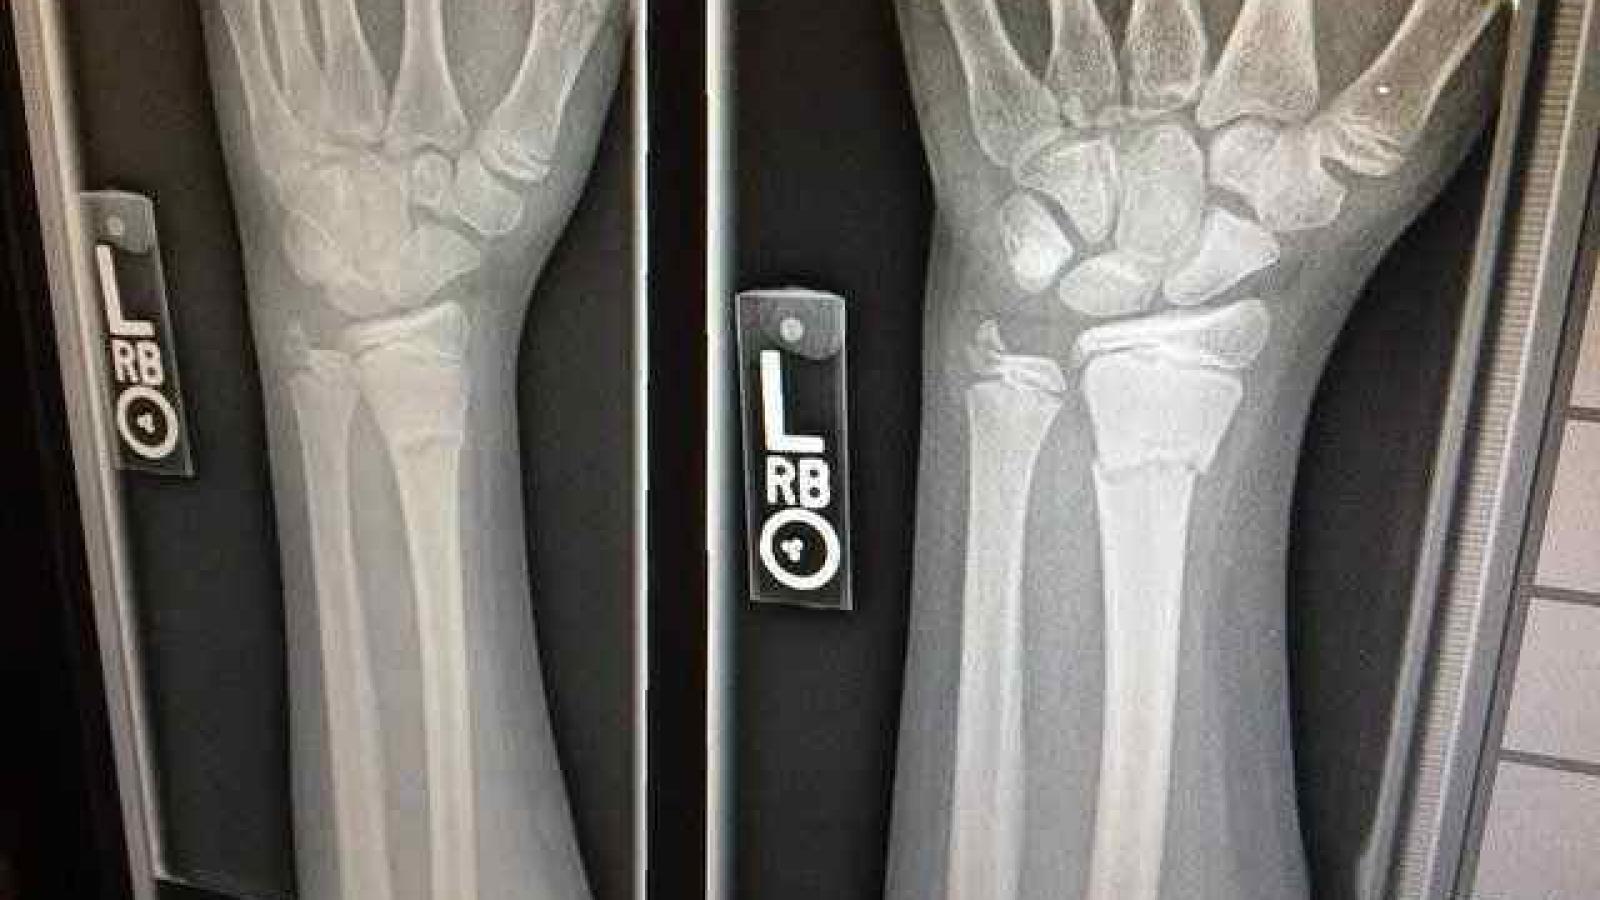

An X-ray